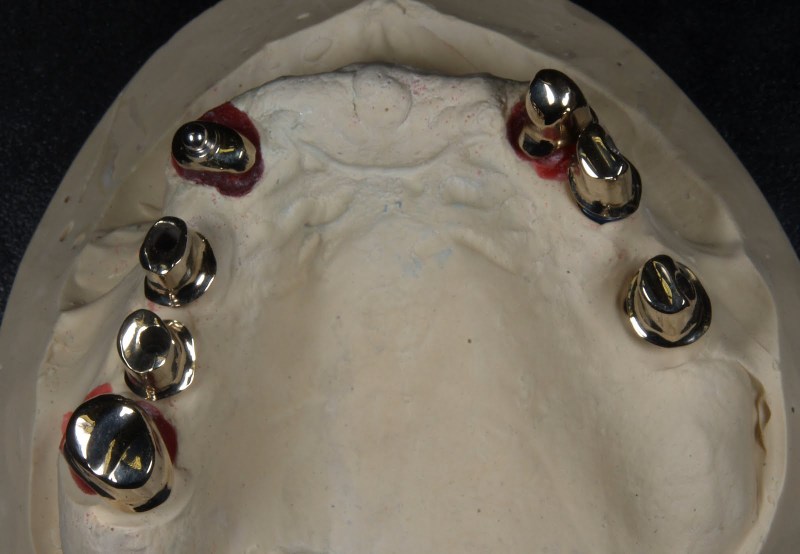

Meisterarbeit von Peter Dengel